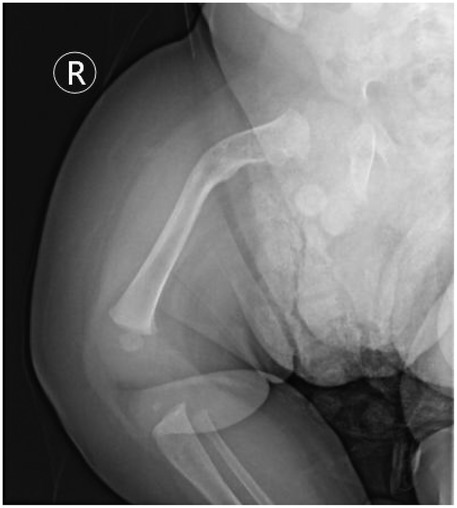

Background: Osteogenesis Imperfecta (OI) poses a unique challenge in pediatric trauma and critical care, where the fragility of bone intersects with life-threatening systemic complications, such as neonatal respiratory failure. The early postnatal period is particularly precarious, demanding a delicate balance between life support and fracture prevention. Case Presentation: A 9-day-old male neonate with prenatally diagnosed COL1A2 (c.1459G>A, p.Gly487Arg) mutation was admitted to our NICU for respiratory distress and pneumonia. He was the progeny of a father with OI, delivered via cesarean section at 34 weeks due to fetal skeletal deformities. Management and Outcomes: A proactive, multidisciplinary team (MDT) protocol was immediately implemented, focusing on non-invasive respiratory support, meticulous handling to prevent iatrogenic injury, and optimized nutrition. This approach successfully resolved his respiratory failure without any new fractures during the NICU stay. However, on the 16th day post-discharge, the infant sustained a spontaneous fracture of the right proximal femur. This was managed conservatively with a Pavlik harness. Follow-up revealed rapid callus formation by day 52 and complete union by day 136, showcasing the characteristic hyperplastic healing pattern of OI. Conclusion: This case underscores that a coordinated MDT approach is vital for stabilizing critically ill neonates with OI. The occurrence of a fracture shortly after discharge highlights the transition to home care as a period of extreme vulnerability. Empowering families with comprehensive education and ensuring continuity of care are as crucial as in-hospital management for improving long-term outcomes in these fragile infants.